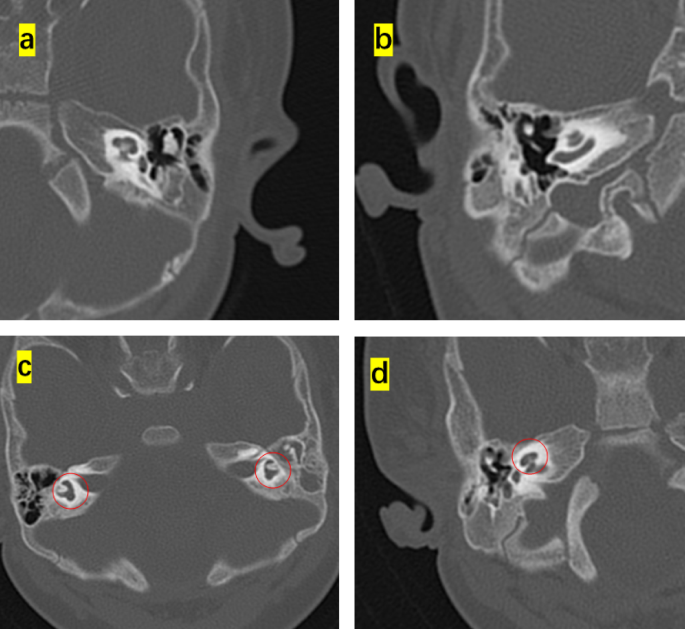

This study enrolled 16 children (8 months to 4 years old) that were diagnosed with diverse phenotypes of syndromic hearing loss and underwent CI. These included six, three, one, and six cases of WS, NS, KS, and CS, respectively. Children with different types of NCP-based hearing loss exhibit unique facial features: the iris of children with WS were heterochromic, and there were no abnormalities in the head and facial structure; the patients with NS had protruding foreheads, widened eye distances, and downward inclination of the eye fissures; the patient with KS had cracks on the long eyelid, with a slight outward rotation of one-third of the lower eyelid and a cup-shaped ear on the right side; all the CS patient were with predominant craniofacial anomalies involving the ears and eyes. Table 1 shows the main clinical features of the 16 children, specifically highlighting the ear malformations and the degree of developmental delay. There were observable differences between the types of syndromic hearing loss. WS and NS showed mild malformations of the middle and inner ear (Figs. 1 and 2). KS (Fig. 3) primarily exhibited malformations of the outer and middle ear structures. CS (Fig. 4) showed significant malformations in the outer, middle, and inner ear and showed varying degrees of stenosis or occlusion of the cochlea in different cases (Fig. 5). Cochlear nerve canal stenosis was observed in almost every CS case. Apart from WS, the other three syndromes showed clear craniofacial malformations, growth delay, and varying degrees of neurodevelopmental delay. Gesell scores were below the normal value of 85. Among the syndromes, WS and NS exhibited mild symptoms, KS showed more pronounced symptoms, and CS cases were the most severe.